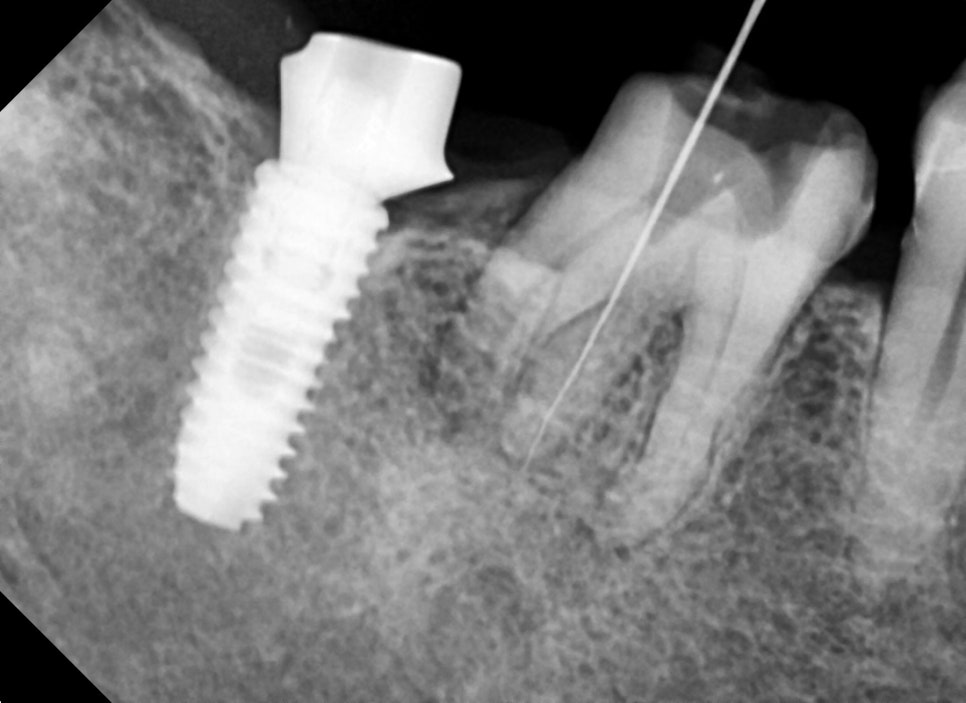

과거에 신경치료를 하시고 크라운을 씌운 상태에서 통증을 느끼셔서 내원해 주셨습니다

엑스레이상에서 뿌리 하방으로 염증소견이 보였습니다.

근관치료를 받으신지 오래되셨고 뿌리 쪽에 기둥도 심어져있어서

재근관치료가 어려워 보였습니다.

오래된 근관치료된 치아의 뿌리 쪽의 오래된 수복 재료는 완벽히 제거하기가 상당히 어렵습니다.

중간중간 사진을 찍어서 확인해가며 제거했고

운이 좋게도 기둥과 뿌리 안의 수복물을 제거할 수 있었습니다.

통상적인 근관치료보다 근관내 소독 횟수를 늘려 염증원을 확실하게 제거하기 위해 노력했습니다.

신경치료가 마무리된 후 엑스레이 사진입니다.

첫 번째 케이스와 마찬가지로 의도하지는 않았지만

뿌리 쪽으로 충전재가 뿌리를 감사고 있는 모습을 보이고 있습니다.

염증에 의해 흡수된 치아 주변 뼈는 추후 천천히 차기를 기대해 보겠습니다.

다행히 증상은 완전히 해결되어 향후 몇 년 동안은 큰 문제 없이 편한 저작활동을 하실 수 있을 것입니다.